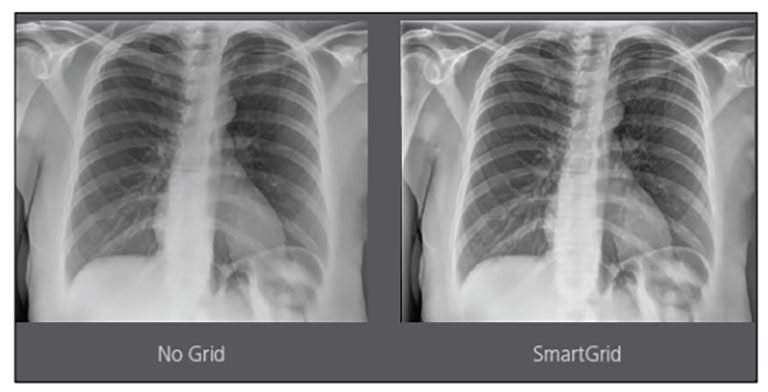

CARESTREAM Image Suite V4 MR11 has set a new standard for workflow efficiency, offering a robust set of features and functionalities to enhance clinical confidence in healthcare professionals. Using an auto-generated companion image from a single exposure, leverage a range of image processing options to increase diagnostic accuracy and enhance patient care.

Bone Suppression